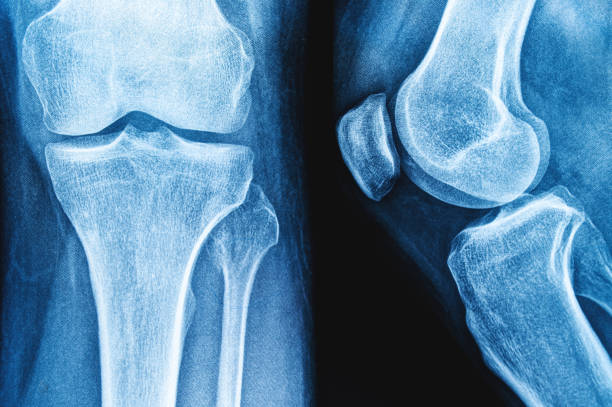

퇴행성 관절염이란?

퇴행성 관절염은 나이가 들면서 관절의 연골이 닳아 없어지고, 관절 사이 간격이 좁아지며 뼈끼리 마찰이 생기는 질환입니다.

주로 무릎, 고관절, 척추, 손가락 관절에서 많이 발생하며,